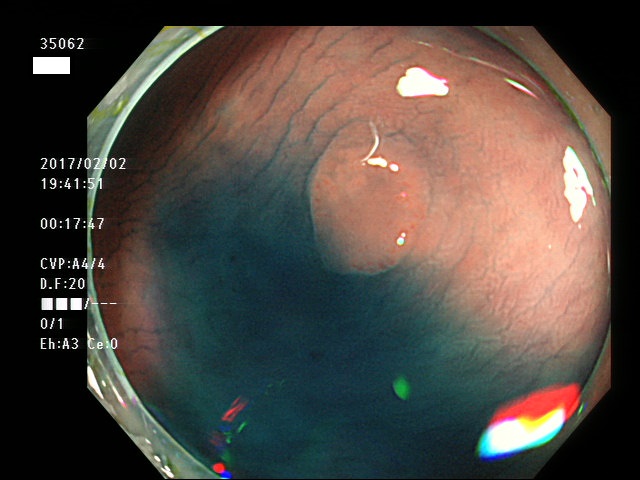

上記100名より抽出した平坦・陥凹型腺腫・SSAP(=癌化の危険が高いが見落としやすい病変)の内視鏡写真

35043 35044 35045 35046 35049 35054 35056 35057 35058 35059 35060 35061